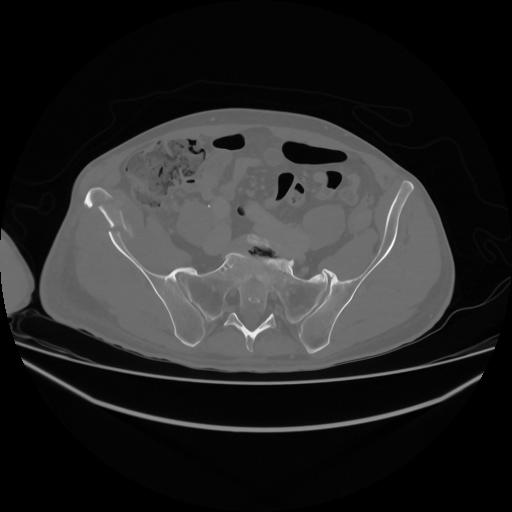

5 CUERPO,CE,Vol,1.0,CUERPO,,